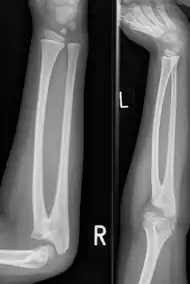

| Congenital radioulnar synostosis in a 7 year old boy | |

Radioulnar synostosis is a rare condition where there is an abnormal connection between the radius and ulna bones of the forearm.[1] This can be present at birth (congenital), when it is a result of a failure of the bones to form separately, or following an injury (post-traumatic).[2]

Diagnosis at birthday is best done using ultrasound technology. In younger children and adults diagnosis is done with x-ray machine at the radioulnar bones.